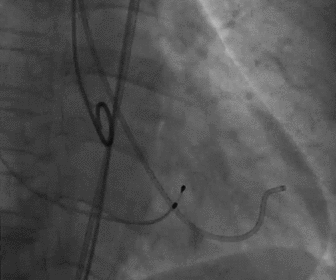

根部造影

球囊预扩

胶囊腔定位

瓣膜释放

造影观察瓣膜形态

手术结果

术后造影及超声探查未见瓣周漏,跨瓣压差术前72mmHg,术后几乎无压差,术中及术后未出现相关并发症,手术圆满完成。